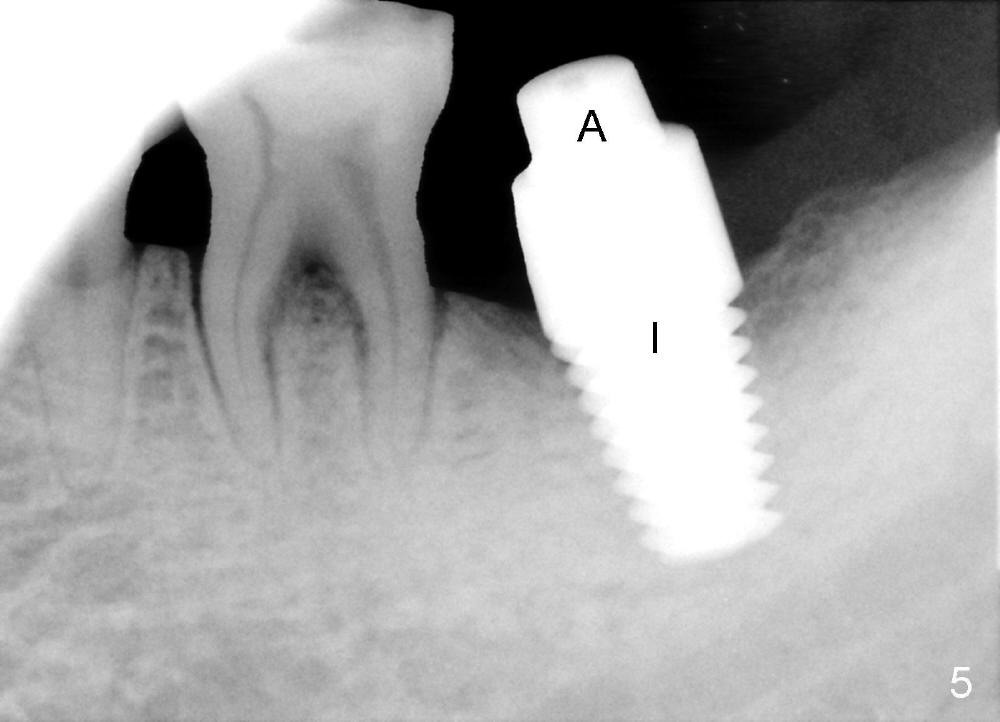

The soft tissue heals around the implant 1 months postop (Fig.1), but the implant (7x11 mm) is unstable. It should have been placed 2 mm deeper (Fig.2). It is splinted for the neighboring tooth (Fig.3). When the splint is removed 4 months later, the implant remains mobile. It is removed with infiltration anesthesia. The osteotomy is deepened by approximately 2 mm. A 7x14 mm tap is inserted with stability (Fig.4); there is apical space to be engaged further (arrowheads). A 7x14 mm implant is placed with insertion torque > 60 Ncm (Fig.5 I); an abutment (A) placed to keep perio dressing in place.